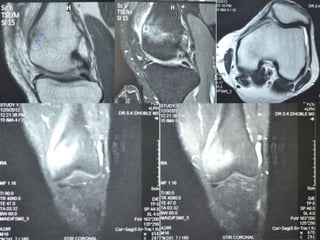

Osteoid Osteoma - MRI

• MRI has not been useful in the diagnosis of

osteoid osteoma.

• MRI is reserved for equivocal cases because it

can suggest the diagnosis of osteoid osteoma.

• MRI interpretation may result in errors in

diagnosis, most often confusion with

malignancies.

Osteoid Osteoma -MRI • MRI has not been useful in the diagnosis of osteoid osteoma. • MRI is reserved for equivocal cases because it can suggest the diagnosis of osteoid osteoma. • MRI interpretation may result in errors in diagnosis, most often confusion with malignancies.